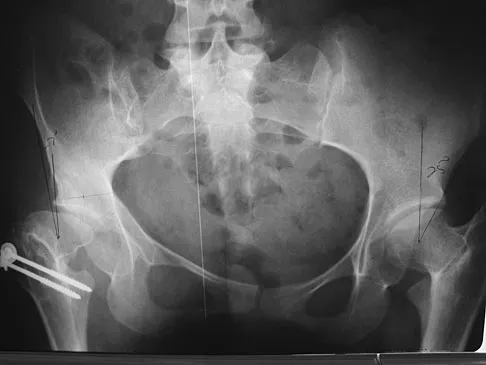

Question 326High Yield

Figures 7a and 7b show the radiographs of a 51-year-old woman who injured her left leg after falling off a stepladder. Surgical reconstruction is performed with a compression screw and side plate; the postoperative radiograph is shown in Figure 7c. Following gradual progression of weight bearing, she reports that she slipped again and placed full weight on the extremity. She now notes a new onset of increased pain in her left thigh and hip region. Follow-up radiographs are shown in Figures 7d and 7e. Reconstruction should consist of

Explanation

The initial fracture was an unstable reverse oblique intertrochanteric fracture with subtrochanteric extension. Initial fixation with a high-angled screw and side plate construct may not provide stability as well as a 95 degree fixed-angle device or a intramedullary hip screw device. The follow-up radiographs show loss of fixation and further propagation of the fracture distally. Reconstruction would best be accomplished with hardware removal and conversion to a long intramedullary nail with femoral head fixation or a 95 degree angled plate and screw device. Conversion to a longer plate does not improve the biomechanical situation at the primary fracture site. In situ bone grafting would not provide any additional stability and would not correct the deformity. The proximal femoral fracture is not amenable to retrograde nailing. Cerclage wiring will not sufficiently enhance stability and is not indicated. Bridle SH, Patel AD, Bircher M, Calvert PT: Fixation of intertrochanteric fractures of the femur: A randomized prospective comparison of a gamma nail and dynamic hip screw. J Bone Joint Surg Br 1991;73:330-334. DeLee JC: Fractures and dislocations of the hip, in Rockwood CA Jr, Green DP, Bucholz RW, Heckman JD (eds): Rockwood and Green's Fractures in Adults, ed 4. Philadelphia, PA, Lippincott-Raven, 1996, pp 1659-1825. Haidukewych GJ, Israel TA, Berry DJ: Reverse obliquity fractures of the intertrochanteric region of the femur. J Bone Joint Surg Am 2001;83:643-650.